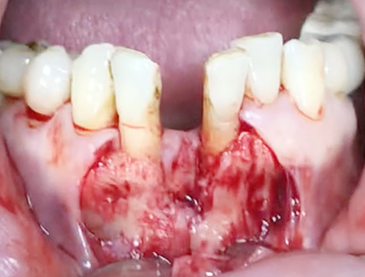

Implants/Bone Grafting

Simultaneous bone graft and implant placement